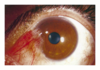

What condition would you consider with this image and buzz words:

- eyelid shows ectropion

- cornea shows neovascularization

- foamy cytoplasm

- clear cytoplasm

Sebaceous Carcinoma

- (Left image) Pagetoid* spread of sebaceous carcinoma. Neoplastic cells with foamy cytoplasm are detected within the epidermis.

- Sebaceous cell carcinoma of the left lower eyelid. (Right Top image) The patient’s left lower eyelid shows ectropion**, and the cornea shows neovascularization.

- (Right Bottom) mild expansion of the conjunctival epithelium due to infiltration by single or small groups of malignant sebaceous cells with large, hyperchromatic nuclei and occasional mitoses. These display little clear cytoplasm reminiscent of sebaceous differentiation

* Pagetoid refers to this spread of neoplastic cells within the epidermis

** ectropion: a condition, typically a consequence of advanced age, in which the eyelid is turned outward away from the eyeball